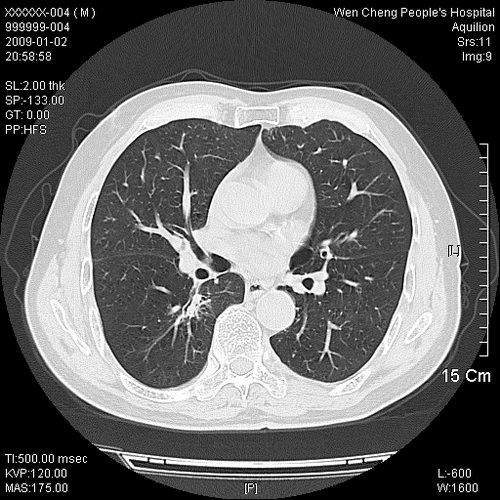

男性,73岁,有慢支病史,肿瘤系列标志物检验正常,血沉及血常规正常

右肺下叶背段小片状 磨玻璃样模糊影,内见血管及含气支气管像,支气管管壁增厚。考虑:慢性炎症!

右肺下叶背段小片状 实性与磨玻璃样影,内见血管及含气支气管像,支气管管壁增厚,边缘见长毛刺影。考虑:慢性炎症或肿瘤!建议抗炎治疗复查,密切观察随访!

右肺下叶片团状影内见扩张的含气支气管和支气管管壁增厚,其周有磨玻璃样模糊影和长毛刺。考虑慢性炎症可能性大。

2、右肺下叶片团状影内见扩张的含气支气管和支气管管壁增厚,其周有磨玻璃样模糊影和长毛刺。考虑周围型肺ca可能,结核不排。

高度提示细支气管肺泡癌,建议抗炎治疗半月观察病灶变化,如无明显改变,建议立即手术治疗.